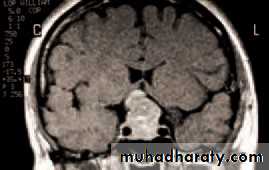

• A CT or MRI scan will help with the diagnosis. Again systemic investigation, for example to determine the site of a primary tumour, may be required.

• Malignant lacrimal gland tumours carry a poor prognosis. Benign tumours still require complete excision to prevent malignant transformation. Optic nerve gliomas may be associated with neurofibromatosis. They

• Fig. 4.5 A CT scan showing a left sided orbital secondary tumour.

• are difficult to treat but are often slow growing and thus may require no intervention. Meningiomas of the optic nerve are rare, and may also be difficult to excise. Again they can be observed and some may benefit from treatment with radiotherapy. Meningiomas from the middle cranial fossa may spread through the optic canal into the orbit. The treatment of lymphoma requires a full systemic investigation to determine whether the lesion is indicative of widespread disease or whether it is localized to the orbit. In the former case the patient is treated with chemotherapy, in the latter with localized radiotherapy.• In children the commonest orbital tumour is a rhabdomyosarcoma, a rapidly growing tumour of striated muscle. Chemotherapy is effective if the disease is localized to the orbit.